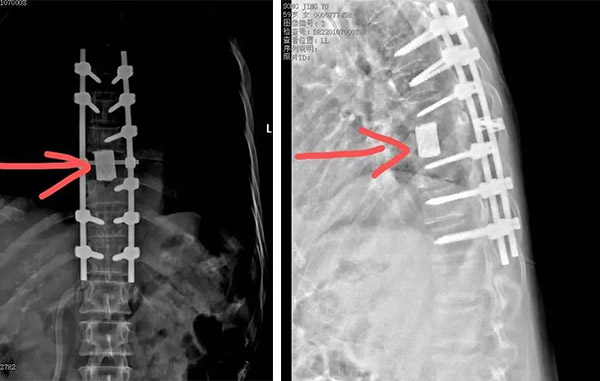

经过周密的术前准备,按照原定计划实施手术。在麻醉科医生的平稳麻醉下,患者取俯卧位,以胸8椎体棘突为中心纵行切口,后路显露胸椎6-10椎板及关节突,暴露胸8椎板以及两侧肋横关节外侧 5-6cm,沿关节突内侧截骨,去除椎板,继续行后路椎体次全切除,沿肋横关节和肋椎关节去除肋骨头,充分游离双侧椎体侧方,骨刀砸断残留椎弓根,继续游离椎体前方,小s钩保护椎前组织,处理一侧肋间血管,胸6.7.11.12椎弓根螺钉固定,上一侧棒,起子剥离上下椎间盘,旋转取出椎体,蒸馏水灭活,椎间钛网骨水泥支撑,维持前柱稳定,固定另一侧棒,双向加压。

胸8椎体切除,解除了脊髓的压迫,恢复了脊柱稳定性

术后一周,李女士可以下地行走,生活能够自理,病情平稳后转入肿瘤科行系统治疗。